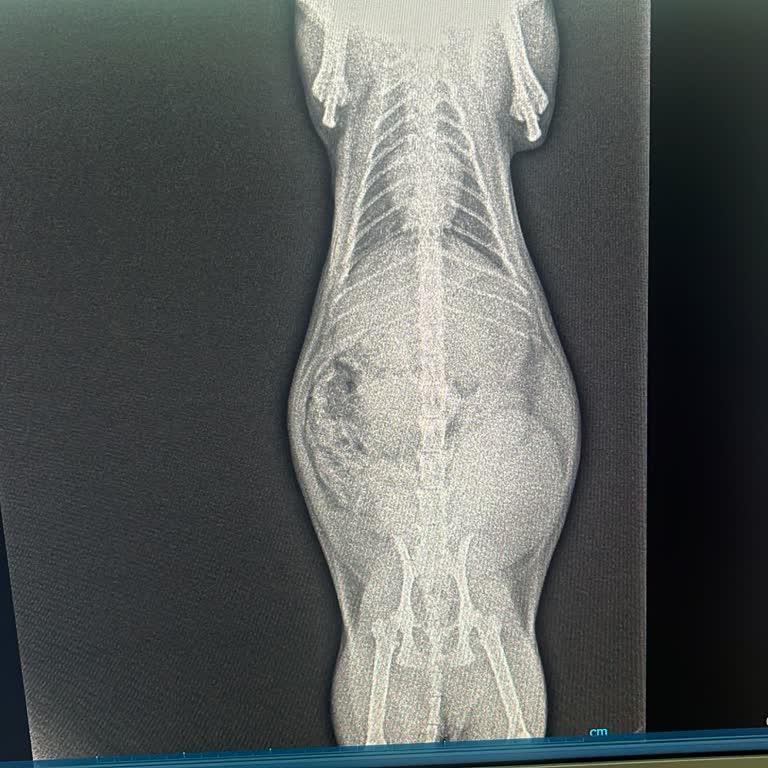

Biricik yavrum Elsa’m 3 gün önce 4 yavru dünyaya getirdi ve 3 gündür tuvaletini yapamadığı, idrarını ise birkaç kez yaptığı için endişelenip daha önce geldiğim Ateş Veteriner'e getirdik. Film, ultrason ve kan tahlili yapıldı. Sonrasında buradaki veteriner Elsa’nın mesanesinin büyümüş ve patlamak üze...